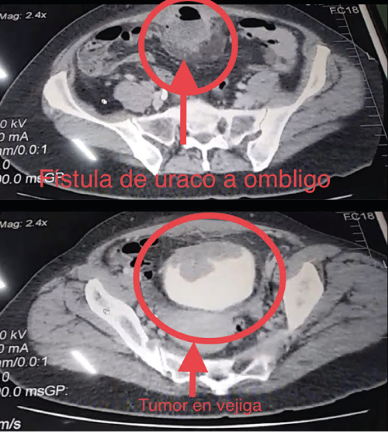

Paciente femenino de 45 años de edad, quien inicia su padecimiento hace 6 años, con múltiples eventos de infección de vías urinarias, recibiendo múltiples tratamientos antibióticos, con mejoría parcial, acompañándose posteriormente con hematuria, mucosuria, y dolor en hipogastrio, con prurito periumbilical y sensación de opresión vesical, con severos síntomas urinarios irritativos bajos, con urgencia miccional, tenesmo, piuria y disuria, motivo por lo que se realiza ecografía de control en medio privado, diagnosticando tumor vesical, por lo que se decide realizar resección transuretral de tumor vesical, en medio privado, con reporte histopatológico de adenocarcinoma de vejiga, sin otros datos, completándose protocolo de estudio con tomografía abdominopélvica contratada, en la que se evidencia tumor en domo vesical, que infiltra pared abdominal anterior, realizándose posteriormente tratamiento con 3 ciclos de quimioterapia, se desconoce el esquema y duración, sin tener respuesta al manejo, presentando desde hace 2 años salida de material purulento por ombligo en abundante cantidad (ver Figura 1).

Con curaciones y drenajes sin mejoría, llegando posteriormente a presentar dificultad para la micción, y mucosuria abundante, acudiendo a nuestra unidad para su valoración, inicialmente se realiza tomografía toraco-abdominopélvica contrastada con fase de eliminación (ver Figura 2).

documentando tumor que involucra techo de la vejiga, pared anterior del musculo recto del abdomen y que se fistuliza al ombligo, sin ganglios, ni metástasis en otros sitios, se realiza cistoscopia de control (ver Figura 3).